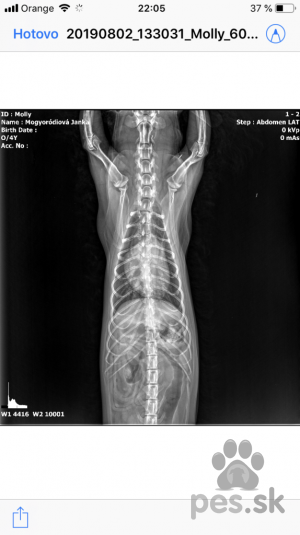

Nasmu 4 rocneme maltezakovy diagnostikovali na zaklade rtg stdca zvacsene srdiecko...u fenky sme si vsimli unavu a ze casto posedava a prestala sa hrat. Chceme sa spytat ci na diagnozu a podavanie luekov staci len rtg srdca, a do akej miery je zvacsene. Ziadne ine priznaky sme si nevsimli.Veterinár radí - bezplatné poradenstvo pre vášho psíka

Nasmu 4 rocneme maltezakovy diagnostikovali na zaklade rtg stdca zvacsene srdiecko...u fenky sme si vsimli unavu a ze casto posedava a prestala sa hrat. Chceme sa spytat ci na diagnozu a podavanie luekov staci len rtg srdca, a do akej miery je zvacsene. Ziadne ine priznaky sme si nevsimli.Odpovede veterinárov